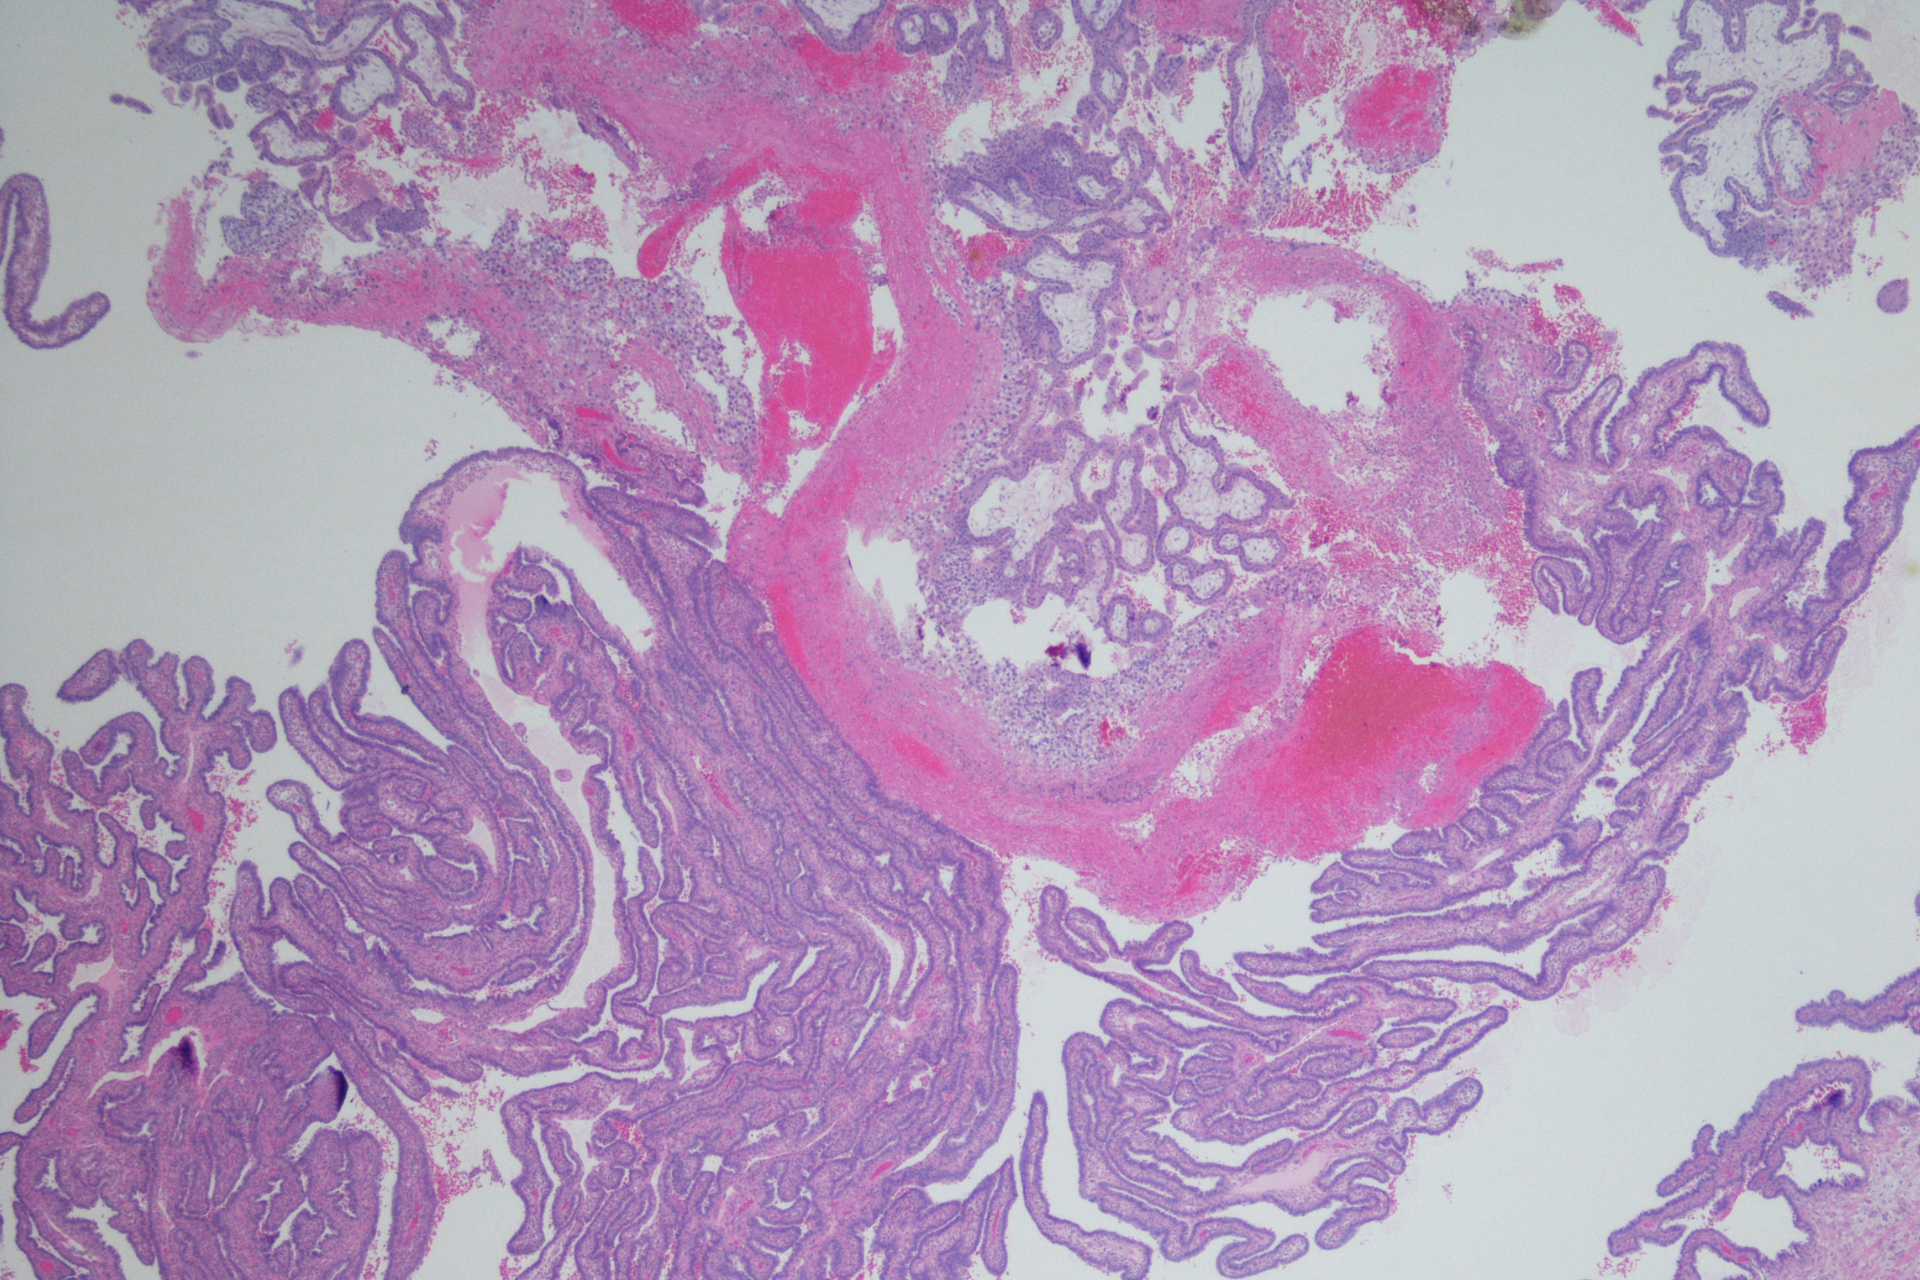

Un embarazo ectópico ocurre cuando el óvulo fecundado se implanta fuera del útero. En la mayoría de los casos, esto ocurre en una de las trompas de Falopio, aunque en situaciones menos frecuentes puede localizarse en el ovario, el cuello uterino o la cavidad abdominal. El útero es el único lugar preparado para que un embarazo crezca de forma segura. Cuando la implantación ocurre fuera de él, el embarazo no puede desarrollarse adecuadamente y puede poner en riesgo tu salud si no se detecta a tiempo.